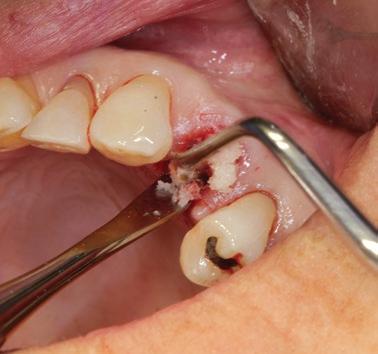

La gestion de l’alvéole post-extraction constitue un défi fréquent en pratique clinique. Lorsqu’un traitement implantaire est envisagé, le contrôle de la résorption osseuse verticale et horizontale devient essentiel afin de préserver les conditions idéales pour un futur positionnement implantaire.

L’objectif de ce module est de permettre une approche rigoureuse de la préservation alvéolaire, en vue d’optimiser le positionnement tridimensionnel de l’implant et de faciliter l’intégration fonctionnelle et esthétique de la restauration prothétique.

Maîtriser les techniques d’extraction atraumatique

Utiliser efficacement les outils diagnostiques (photographie, imagerie, etc.)

Comprendre les objectifs et indications de la préservation alvéolaire

Sélectionner les biomatériaux appropriés (substituts osseux, membranes) et les techniques de suture

Évaluer les indications de temporisation et choisir la solution adaptée

Pratiquer les techniques de préservation alvéolaire en atelier